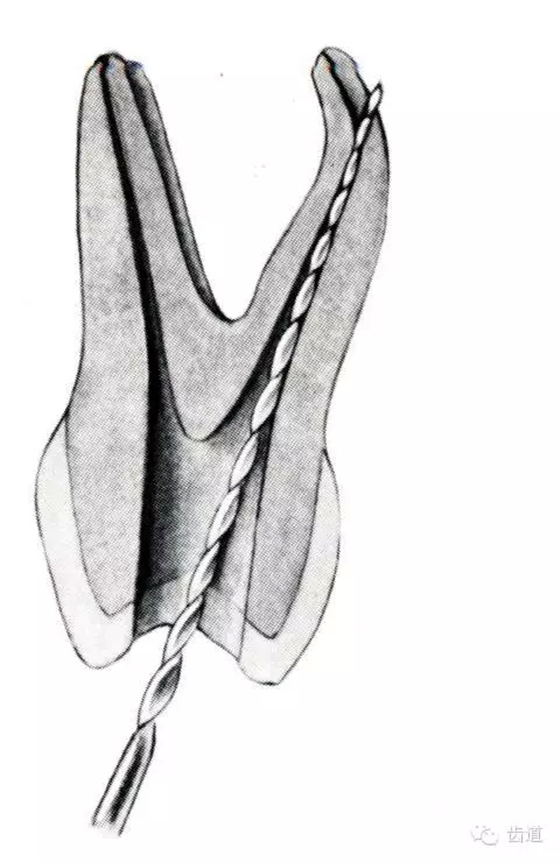

3.使用機(jī)用根管器械,應(yīng)支點(diǎn)穩(wěn)、轉(zhuǎn)速慢,并只能應(yīng)用于直的根管。

4.制備開髓洞形時(shí),應(yīng)充分暴露根管口,對(duì)彎曲根管能盡量減少其彎曲度,對(duì)彎曲度在30o以上的根管盡量采用超聲根管預(yù)備并使用鎳鈦根管挫。